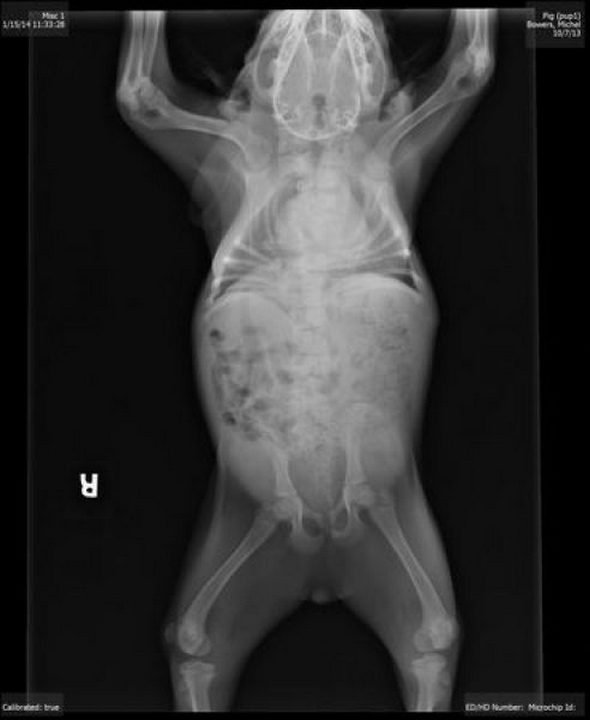

Собака, у которой нет шеи

Хрюшка родилась от дикой матери в лесу на северо-востоке Атланты, штат Джорджия. Несмотря на серьезные дефекты, собачка выжила благодаря заботе Ким Дилленбек, проработавшей не один год с больными животными. Теперь Хрюшка стала настоящей интернет-сенсацией.